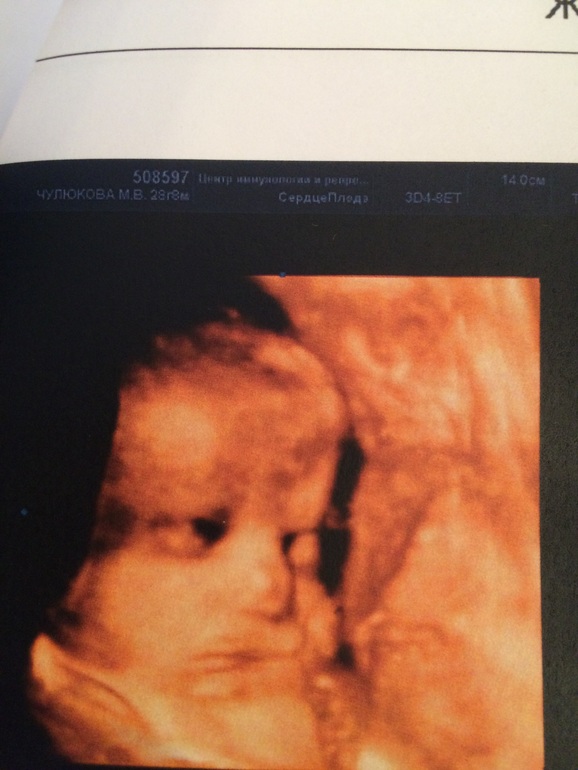

А мы сегодня были на УЗИ)))

УЗИ, КТГ, доплерОпять ездили в ЦИР в Марьино Все у нас хорошо, все в пределах нормы.Под вопросом только почки...Как и в прошлый раз расширение лоханок обеих почек...Мочеточники не расширены, неизвестно, в чем причина этого...врач-узист порекомендовала съездить в Филатовскую больницу, когда Ксю уже родится и проверить-посмотреть, что и как...Но говорит, что не исключает того, что все еще наладится...

В остальном - абсолютная норма; 1709г 41 см...Головное предлежание, обвитий нет.Как и Юля закрывалась ручонками, но все-таки на минутку ручку убрала и мы ее рассмотрели)))

Вот такая вот наша Ксю)))Обещают, что девчоночка волосатенькая родится)))

А где же фото животика?)))вот это фотка с узи-прям супер кадр))надо же как поймали)))